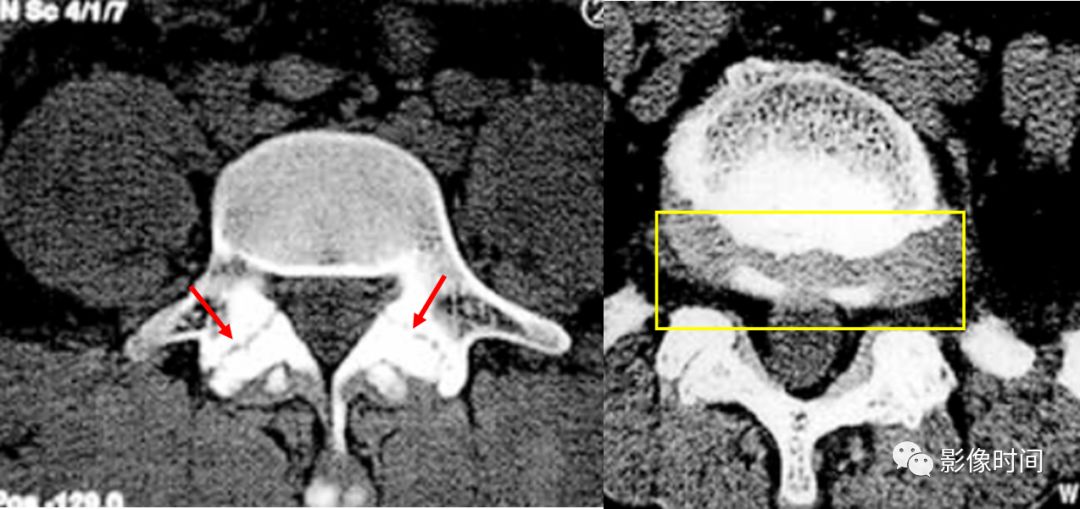

3双边征

双边征是脊柱前滑脱的 CT 表现之一,指的是在横轴位图像上,上位滑脱椎体下缘与下位椎体上缘显示于同一层面,位置一前一后,呈「双边」样。常见于腰椎椎弓峡部裂伴椎体滑脱。

典型病例

腰椎椎弓峡部裂并椎体滑脱。CT 示双侧椎弓峡部裂隙(红箭),并可见双边征(黄框)。

引用自:张杰,卜庆丰. 腰椎椎弓峡部裂的 CT 诊断. 中国医学影像学杂志,2005,13(6):467-468.